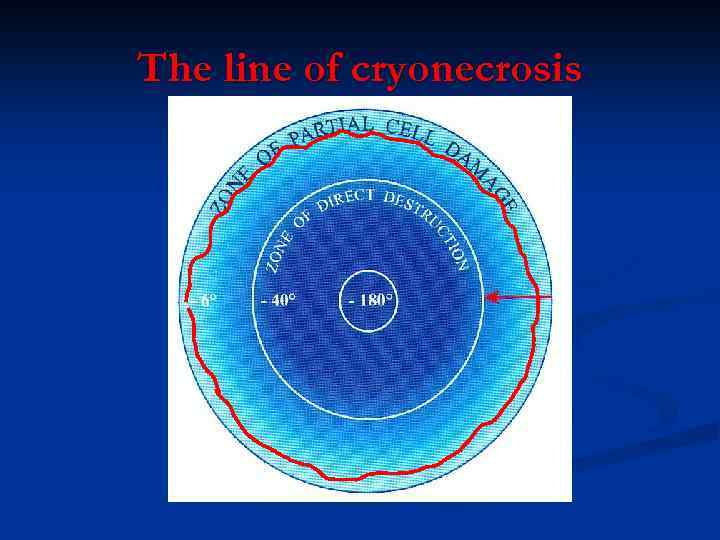

Проблема: Структура криохирургического ледяного шара не однородна

Проблема: Структура криохирургического ледяного шара не однородна

The line of cryonecrosis

The line of cryonecrosis